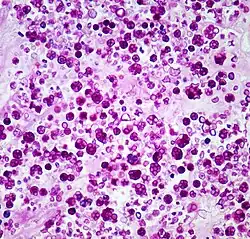

Histologic stain of a Prototheca zopfii infection in a dog | |

Protothecosis, otherwise known as Algaemia, is a disease found in dogs, cats, cattle, and humans caused by a type of green alga known as Prototheca that lacks chlorophyll and enters the human or animal bloodstream. It and its close relative Helicosporidium are unusual in that they are actually green algae that have become parasites.[1] The two most common species are Prototheca wickerhamii and Prototheca zopfii. Both are known to cause disease in dogs, while most human cases are caused by P. wickerhami.[2] Prototheca is found worldwide in sewage and soil. Infection is rare despite high exposure, and can be related to a defective immune system.[3] In dogs, females and Collies are most commonly affected.[4]

Disseminated protothecosis is most commonly seen in dogs. The algae enters the body through the mouth or nose and causes infection in the intestines. From there it can spread to the eye, brain, and kidneys. Symptoms can include diarrhea, weight loss, weakness, inflammation of the eye (uveitis), retinal detachment, ataxia, and seizures.[11]

Dogs with acute blindness and diarrhea that develop exudative retinal detachment should be assessed for protothecosis.[6] Diagnosis is through culture or finding the organism in a biopsy, cerebrospinal fluid, vitreous humour, or urine. Treatment of the disseminated form in dogs is very difficult, although use of antifungal medication has been successful in a few cases.[4] Prognosis for cutaneous protothecosis is guarded and depends on the surgical options. Prognosis for the disseminated form is grave. This may be due to delayed recognition and treatment.[3]